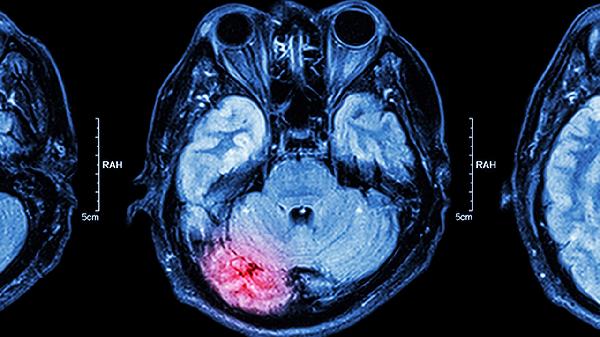

脑CT检查是临床常用的影像学检查手段,通过X射线对人体头部进行断层扫描,能够清晰显示脑组织结构。单次脑CT检查的辐射剂量约为2-10毫西弗,远低于可能致癌的100毫西弗阈值。现代CT设备采用智能剂量调节技术,可根据检查部位自动优化辐射剂量,进一步降低风险。对于需要重复进行脑CT检查的患者,医生会严格评估检查的必要性,确保累积辐射剂量在安全范围内。